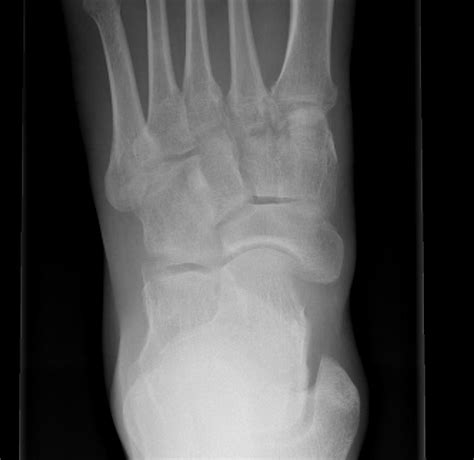

Diagnosing Accessory Navicular Bone

Diagnosing an accessory navicular bone involves a combination of physical examination and imaging tests. A healthcare professional will typically perform the following steps:

• Physical Examination: The doctor will examine the foot, checking for tenderness, swelling, and any visible deformities.

• Imaging Tests: X-rays, MRI, or CT scans may be ordered to visualize the accessory navicular bone and assess its structure and connection to the navicular bone.

These diagnostic tools help determine the type of accessory navicular bone and the extent of any associated symptoms.